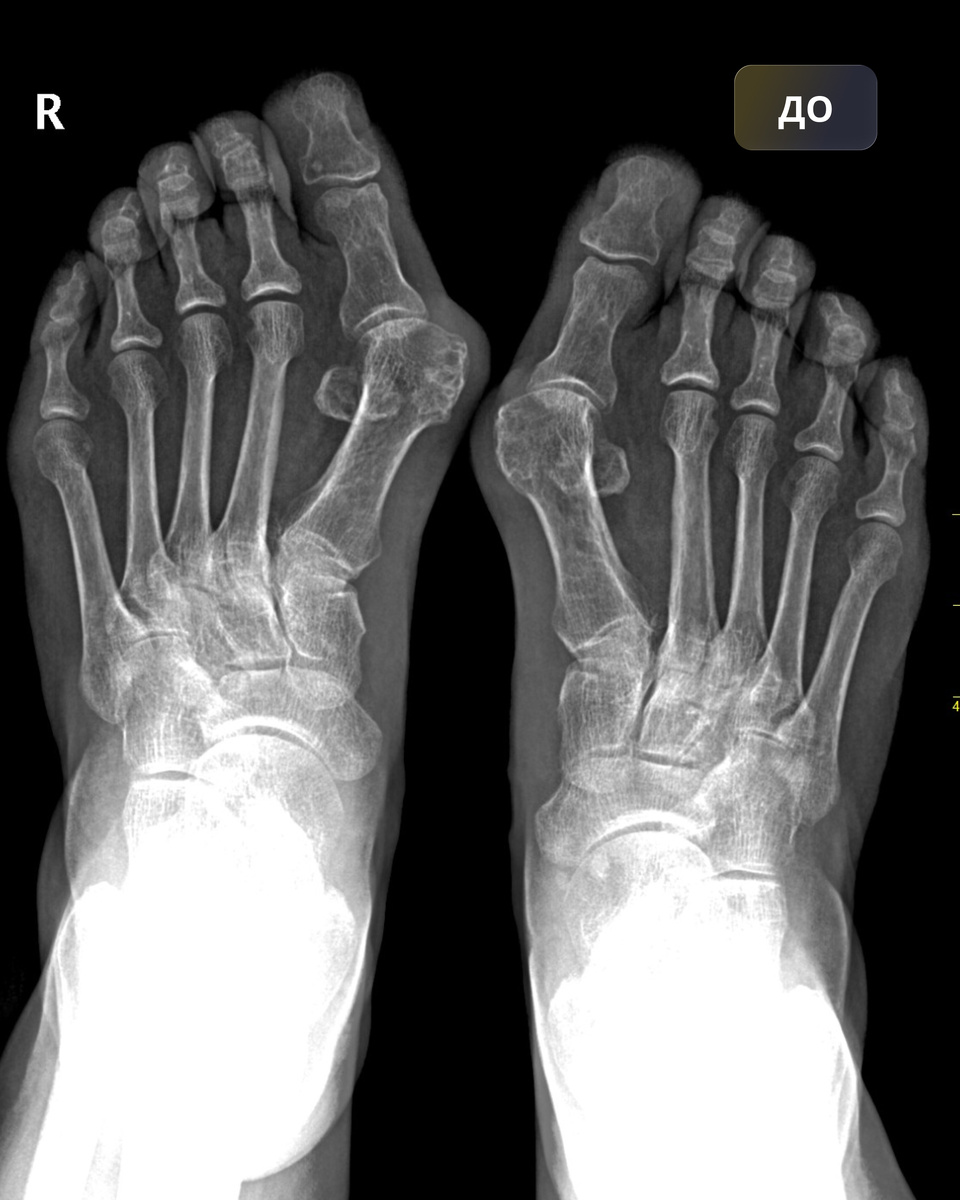

Пример хирургического вмешательства по поводу Hallux Valgus

Сегодня я хочу показать один из примеров хирургического вмешательства одного из пациентов. Фотографии До и После доступны в публикации.